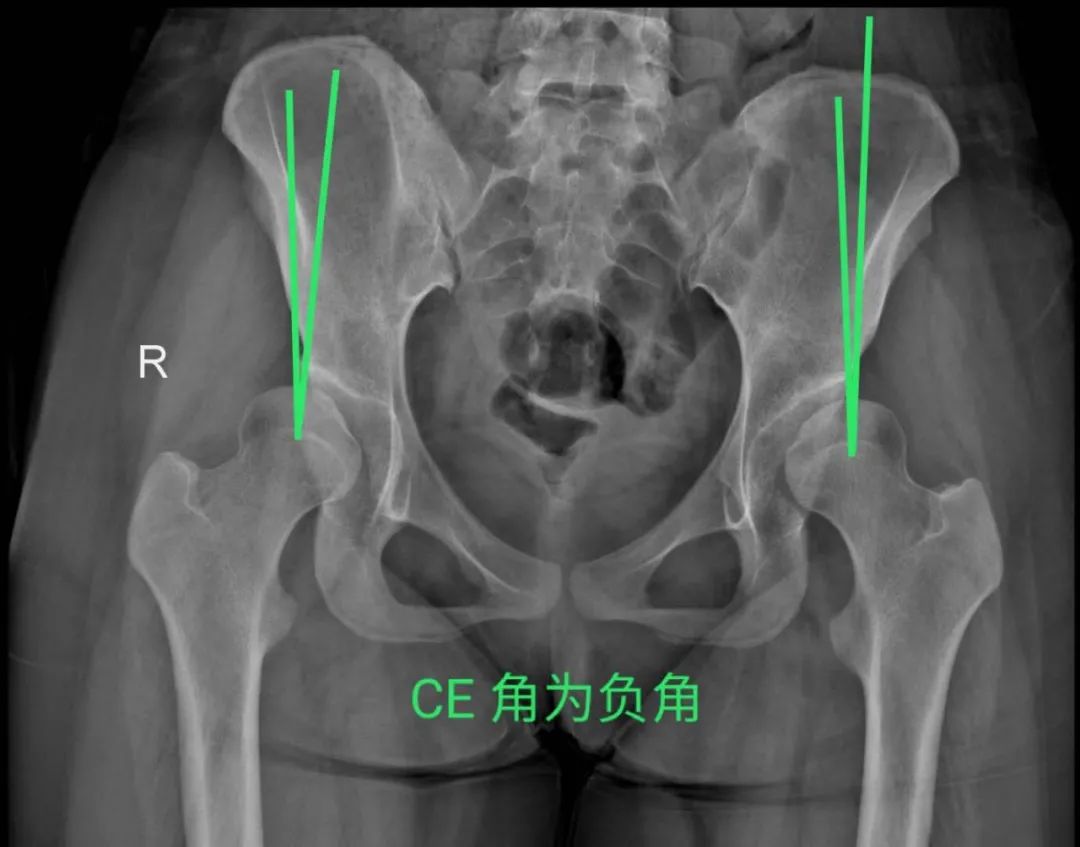

今年15歲的孫某,出現(xiàn)雙側(cè)髖部疼痛,呈持續(xù)性隱痛,只采取口服藥物的保守治療,但是疼痛未見減輕反而愈演愈烈,于是到誠德骨科醫(yī)院集團(tuán)(市中院區(qū))尋求專家的幫助,經(jīng)過多方檢查和論證后,劉德俊院長診斷為:

先天性多發(fā)性骨骺發(fā)育不良,并決定為其實施“髖臼周圍截骨術(shù)”。

據(jù)了解,髖關(guān)節(jié)發(fā)育不良是引起繼發(fā)性髖關(guān)節(jié)炎的重要致病因素之一,髖臼周圍截骨術(shù)能夠有效改善髖臼覆蓋、增加負(fù)重關(guān)節(jié)面,內(nèi)移髖關(guān)節(jié)的旋轉(zhuǎn)中心,從而減小髖關(guān)節(jié)負(fù)重面軟骨應(yīng)力,達(dá)到預(yù)防和推遲骨關(guān)節(jié)炎發(fā)生的目的。